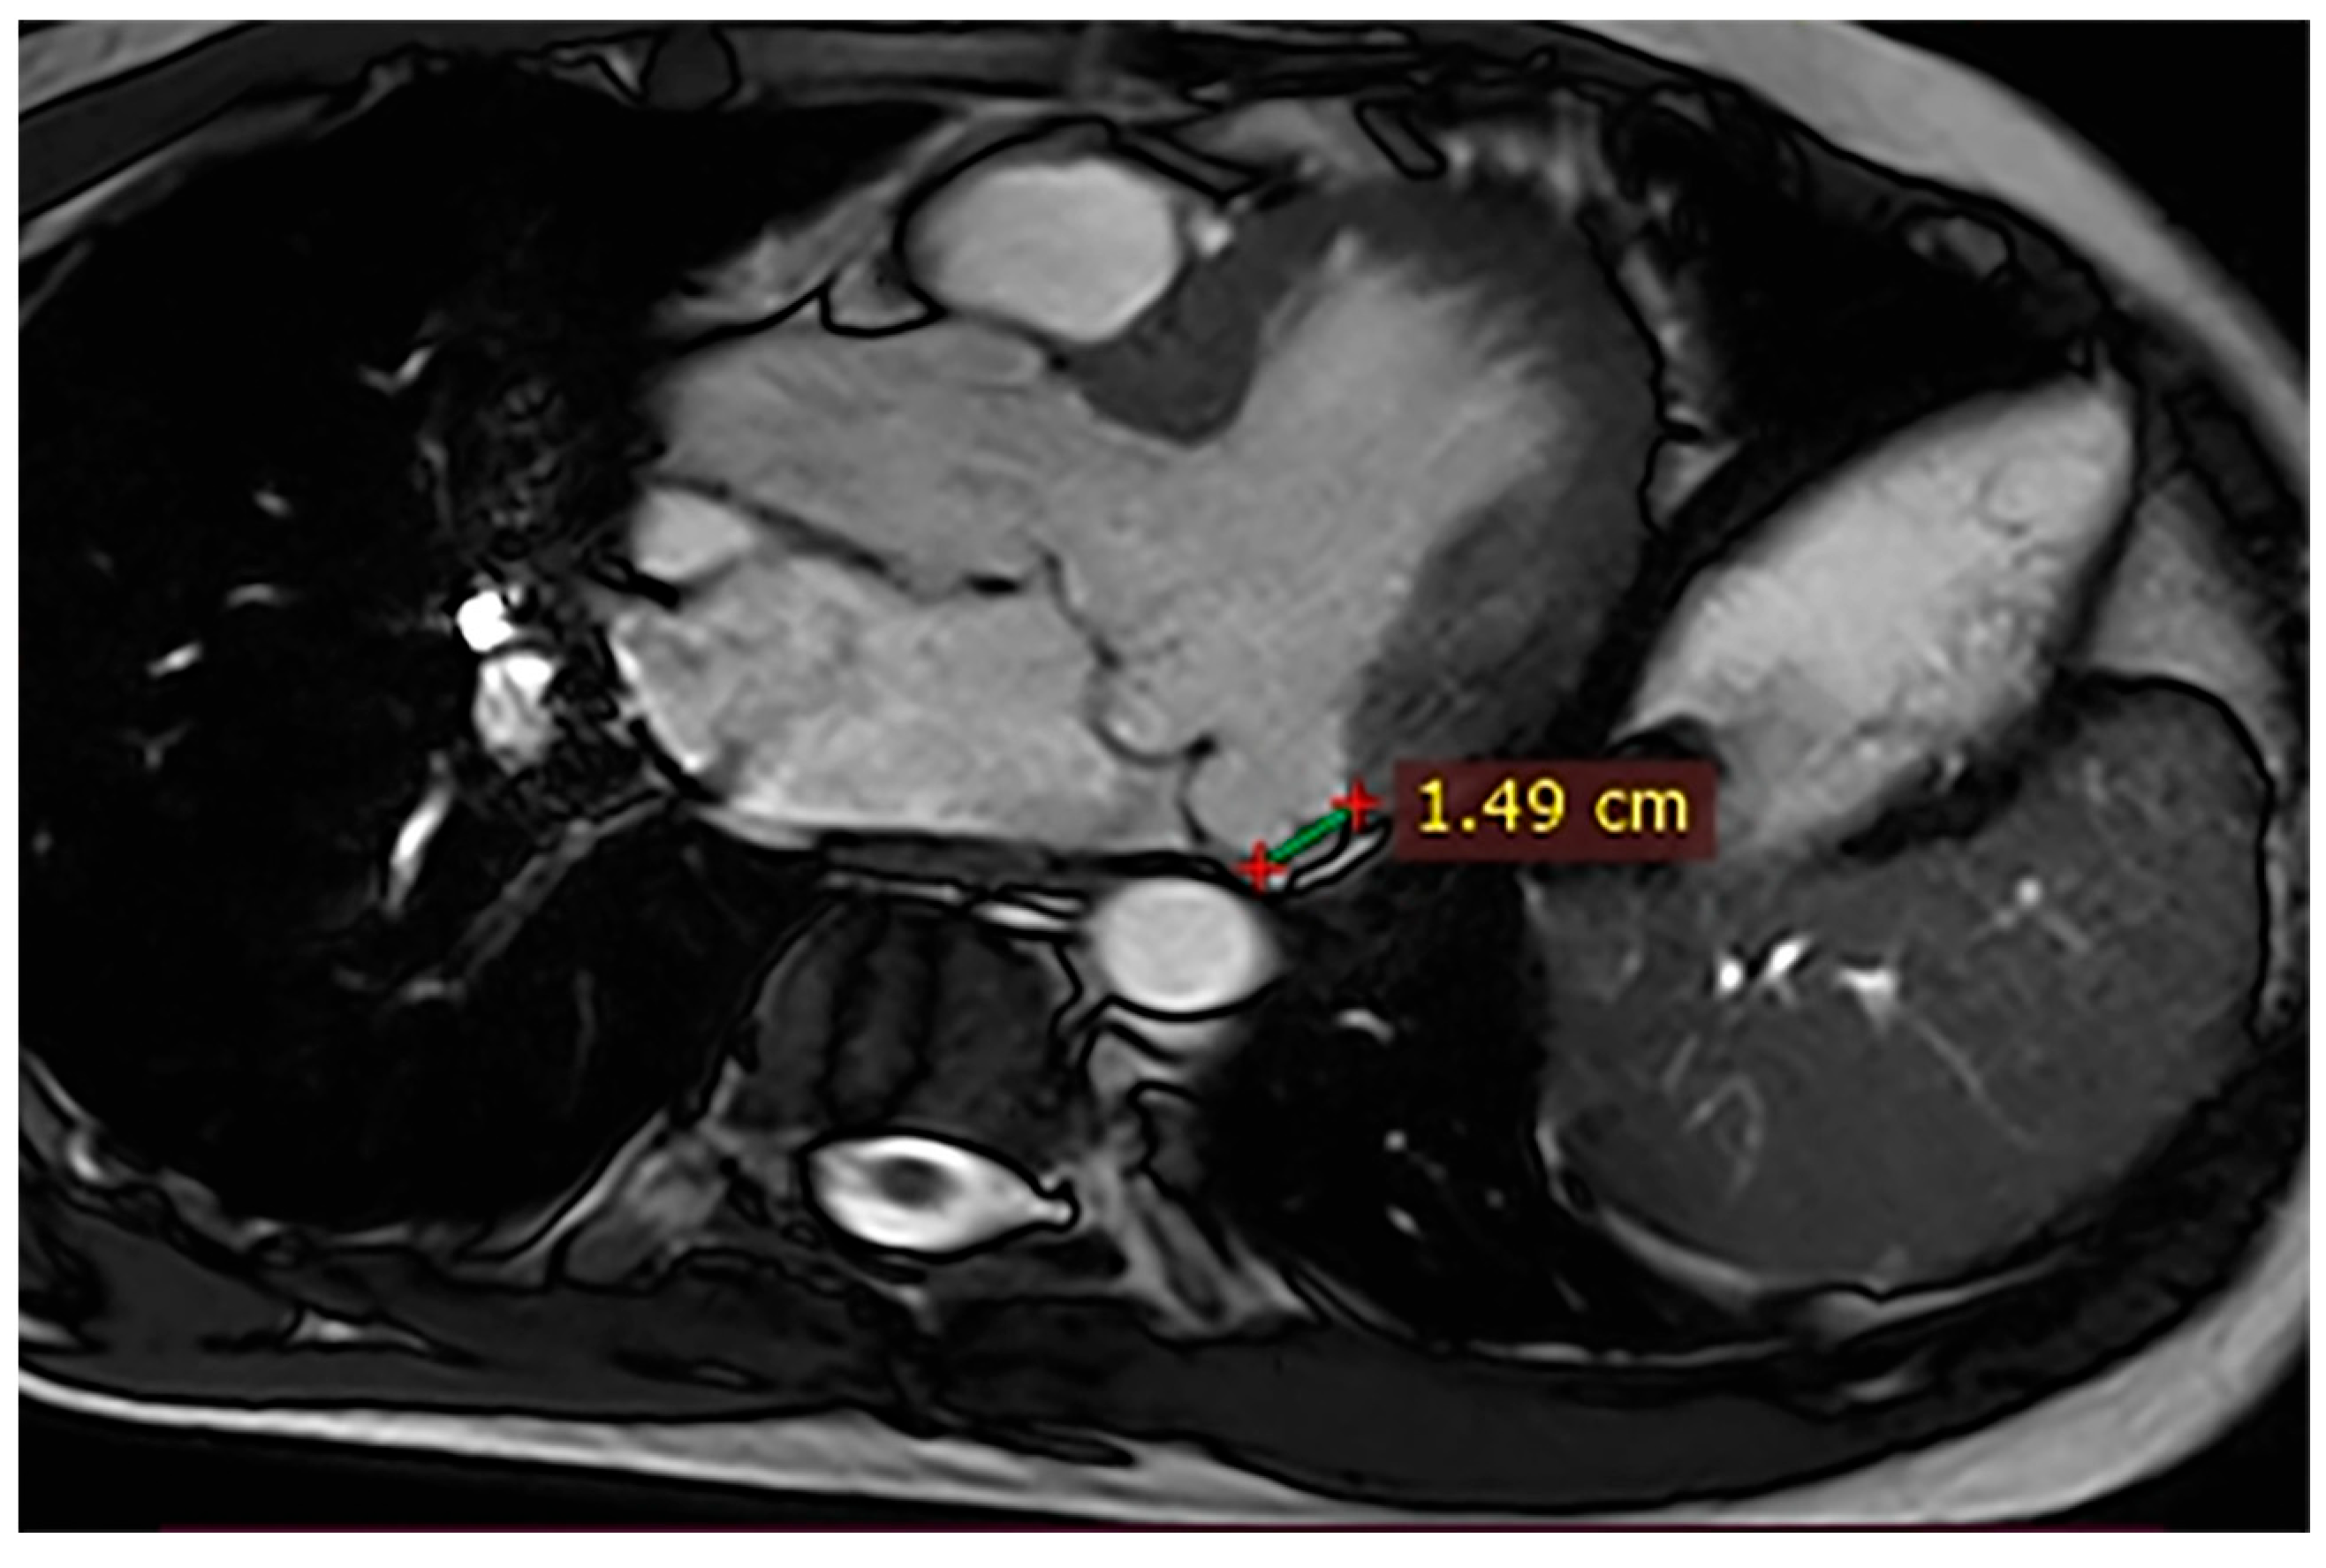

Case 7. A 53-year-old woman with syncope and premature ventricular contractions had normal LVEF (55%) on CMR, a 15 mm MAD associated with MVP and mitral regurgitation (Figure 6), and non-ischemic LGE in the basal lateral segments. Given the coexistence of extensive MAD, MVP, and fibrosis, an increased arrhythmic risk was considered, and antiarrhythmic therapy was discussed.

Figure 6.

Cardiac magnetic resonance (CMR), three-chamber steady-state free precession (SSFP) cine. A 15 mm mitral annular disjunction (MAD) is observed.